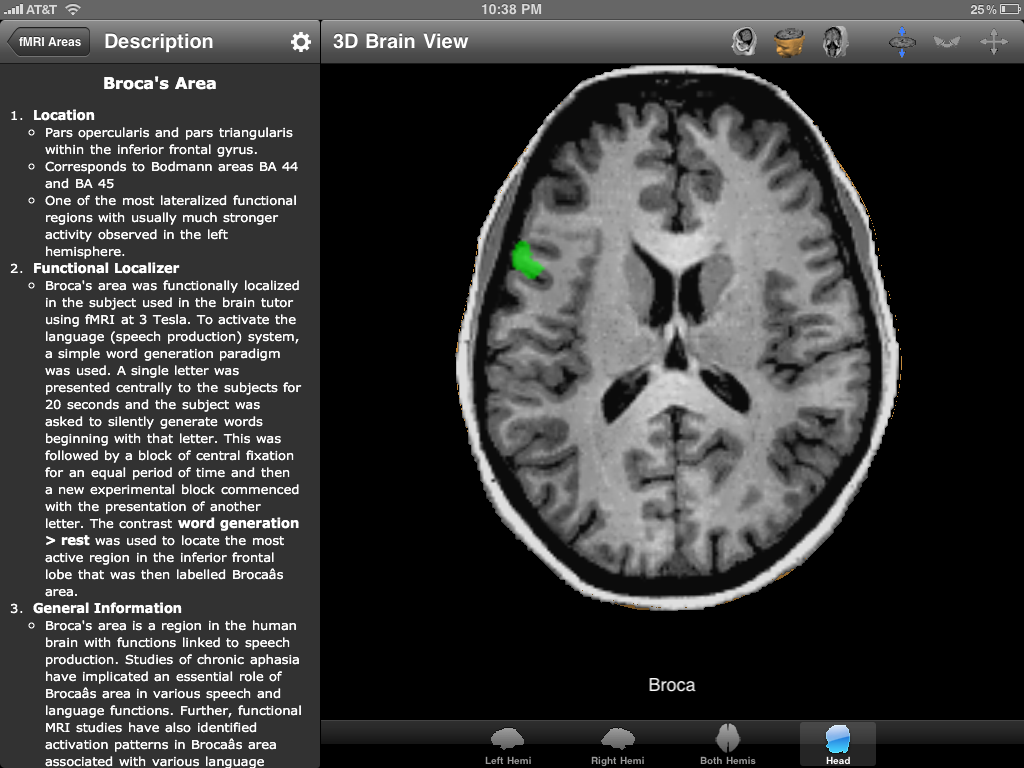

The program information divided into five atlases, namely Lobes, Gyri, Sulci, Brodman Areas and Functional Areas. Each atlas contains numerous structures appropriate to its parent category. As the structures in the atlas are selected, the corresponding areas in the 3D brain representation are highlighted. Each entry also provides an arrow which loads the description and displays information such as the nomenclature, location, function and connectivity.

In addition to computer-generated models of the neuroanatomy, the program also provides MRI imaging in the form of a 3D rotatable head created with the BrainVoyager software package. In this depiction, the same rules as earlier apply. As each structure is selected, the corresponding area in the MRI lights up showing the appropriate anatomy. Coronal, transverse and sagittal views are all available.

in that it does provide real-world MRI images of the brain in a moving cross section. Flipping through the cross sections of the brain feels a lot like viewing the images on a computer in the hospital and really helps with learning the anatomy as it exists in three dimensions.